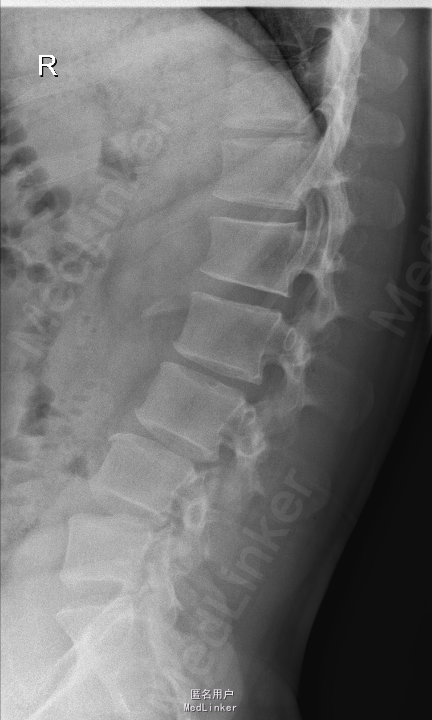

查体:腰部叩痛,腰部活动受限,左侧膝内侧、小腿外侧、内踝、足部感觉减退,右侧小腿、足背感觉减退,屈髋、伸膝、踝背伸肌肌力左侧4级,右侧4-5级,踇背伸、跖屈肌肌力左侧3-4级,右侧4级,双侧膝腱反射+,跟腱反射+,双侧巴氏征阴性,直腿抬高试验左侧40°阳性,右侧阴性。 辅助检查: X-ray:腰椎退行性变,多节段不稳 CT:腰椎间盘突出并椎管狭窄伴钙化,腰2-3,3-4,4-5,腰5骶1 MR:腰椎间盘突出并椎管狭窄,腰2-3,3-4,4-5,腰5骶1 上传受限无法全部上传,见谅

诊断:腰椎间盘突出症并椎管狭窄 处理:1、完善相关辅助检查,明确诊断,有无手术指证; 2、完善手术评估,有无手术禁忌,手术风险及并发症; 3、在全麻下行腰椎后路多节段减压椎间植骨融合内固定术 4、腰2-3,腰3-4行开窗减压,腰4-5,腰5-骶1行椎间Cage植骨融合